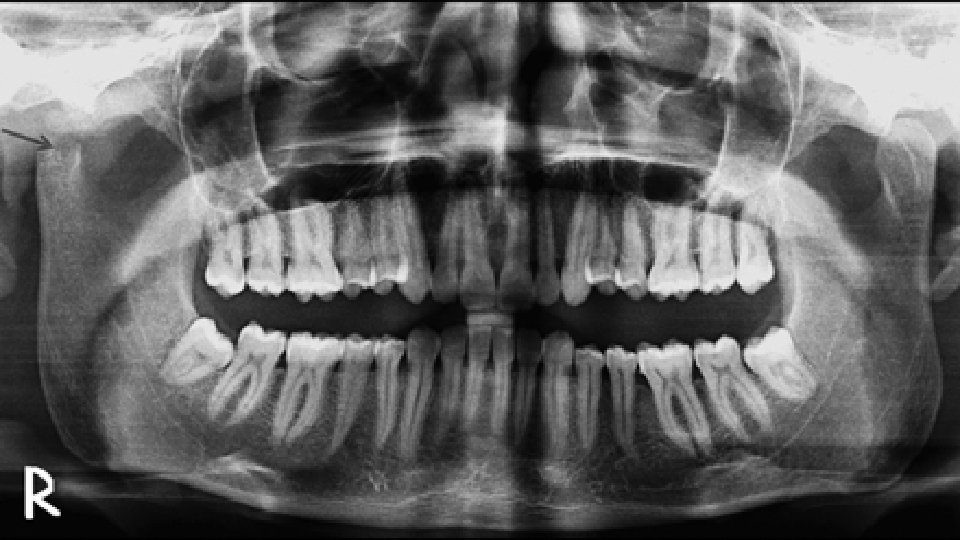

Osteomüeliit • Tuleneb kreeka keelest – „osteon“, tähendab luud, „myelo“- tähendab üdi, ja –“itis“ tähendab põletikku • Luu põletik ja infektsioon – võib kaasneda ka üdi, koore, periosti, pehmete kudede haaratus • Lõpptulemusena toimub luu hävitamine • Enamasti bakteriaalne

Akuutne, subakuutne, krooniline • Akuutne – suppuratiivne infektsioon, avaldub tursena, väikeste veresoonte tromboosina, vaskulaarkongestioonina 2 nädala jooksul algusest • Subakuutne- rahulikuma, aeglasema kuluga osteomüeliit – avaldub alles ühe kuni mitme kuu jooksul • Krooniline- pikaaegse infektsiooni tulemus, võib kuluda kuid või aastaid kujunemiseks, võib olla peremehe poolt allasurutud(remissioonis)või osaliselt ravitud – jääb „magavasse“ olekusse pikaks ajaks enne kliinilist avaldumist. Esineb nekrootiline luu, uue luu teke, drenaaž või fistulid, leukotsüütide, lümfotsüütide, histiotsüütide kohalolek.